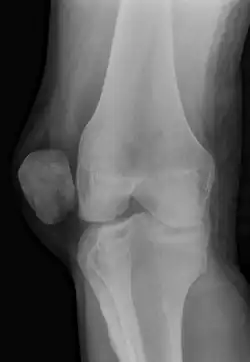

A patellar dislocation typically occurs when the knee is straight and the lower leg is bent outwards when twisting.[1][2] Occasionally, it occurs when the knee is bent and the patella is struck directly.[1] Commonly associated sports include soccer, gymnastics, and ice hockey.[2] Dislocations nearly always occur away from the midline.[2] Diagnosis is typically based on symptoms and supported by X-rays.[2]

Diagnosis

On X-ray, with skyline projections, dislocations are readily diagnosed. In borderline cases of subluxation, the following measurements can be helpful: